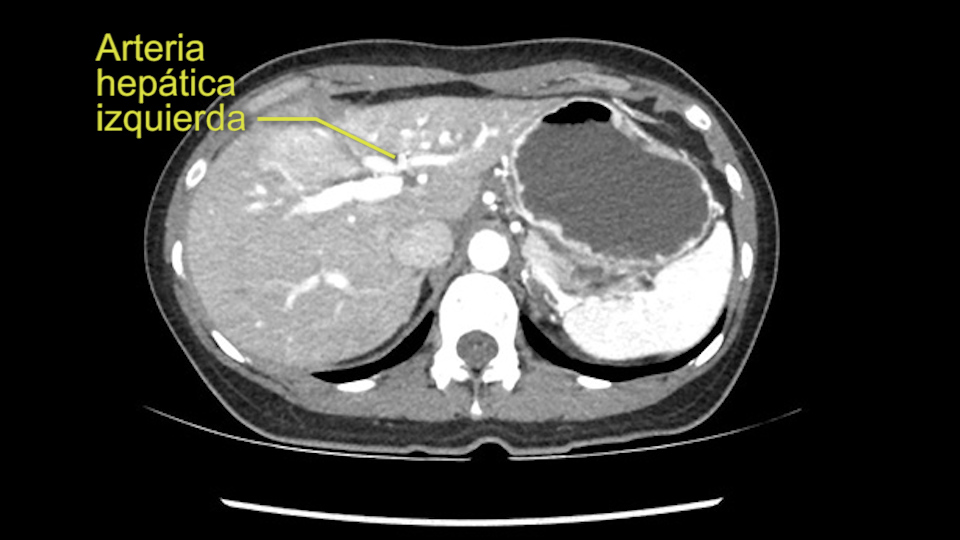

So I have to say that I would do this open, not laparoscopically because of the size of the tumor itself. Upper abdominal incision. Almost certainly, we’d be able to flip this very exophytic lesion up. Intraoperative ultrasound will show the relationship of the tumor and the left portal vein but the dissection at the base of the liver, as I look at things here, I can see the left hepatic artery which sneaks up to the left of the portal vein, should be out of harm’s way so I can take the Segment 2-3 left hepatic artery. The left portal vein is somewhat compressed. But by the time you pull the liver up a bit, you’ll be able to pull that left portal vein out to length and get a good margin on it.

Muchas ramas de la arteria hepática izquierda al tumor

En cuanto a la técnica quirúrgica lo primero que hago es mirar al escáner a la fase arterial que tenemos aquí y claramente ese ve como los hepatocarcinomas son tumores muy vascularizados se pude como las ramas de la arteria hepática izquierda hay muchas ramas nutriendo a este tumor, parece que son bastantes grandes. Parece claro que todas las ramas yendo al hígado derecho están libres de tumor y yo no creo que haya ninguna invasión vascular en este caso. Y como se puede ver hay una gran masa que insisto parce que cuelga del segmento 3.

En cuanto a la hepatectomia izquierda aquí creo que la clave va a ser disecar bien el ligamento venoso y poder ir pasar una cinta alrededor de la vena hepática izquierda, en este caso parece que al vena hepática izquierda está muy junta, como en muchos casos a la vena hepática media, a ser importante disecar bien la vena supra hepática izquierda para poder pasar alrededor de ella sin dañar la cava o la vena hepática media. Una vez que hayamos hecho esto pasaremos a mirar la porta, y yo siempre tiendo a disecar las estructuras lo mas próximas al hígado posible, disecaremos la arteria hepática media rama del segmento 2-3 y la rama del segmento 4 si estamos haciendo una hepatectomia izquierda, y insisto parce que este tumor además tiene otras muchas ramas que van directas al tumor que habrá que ligar, eso nos dará acceso a la vena porta izquierda que probablemente resecare con una grapadora lineal, y finalmente transectarmos, haremos la transeccion hepática.